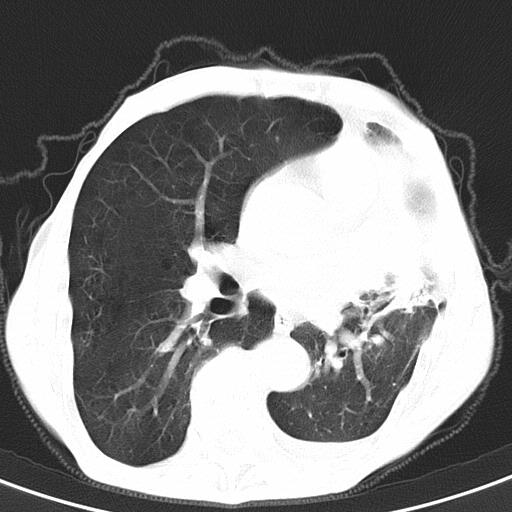

患者78岁,咳嗽胸闷一年余,近月来左侧胸痛;

建议强化,首先考虑左肺癌胸膜转移。

左侧少量胸腔积液,局限胸膜增厚,结合病史,考虑慢性肺炎.

患者左侧胸廓塌陷说明是长期病变,考虑tb性胸膜炎可能性大,另外有明显的肺气肿,建议行结核菌素实验,或者增强扫描

1.慢支肺气肿。2.左肺感染,建议治疗后复查。3.左侧少量胸水。

1.慢支肺气肿。2.左肺感染,建议治疗后复查,待除外继发性肺结核合并感染。3.左侧少量胸水。

1)考虑左肺慢性感染性病变(结核可能)。2)左肺上叶周围型肺癌不排除;建议追踪复查。3)肺气肿。4)左侧胸腔积液,左侧胸膜增厚、粘连。

1)考虑左肺慢性感染性病变(结核可能)。2)肺气肿。4)左侧胸腔积液,左侧胸膜增厚、粘连。3)左肺上叶周围型肺癌不排除;建议追踪复查。